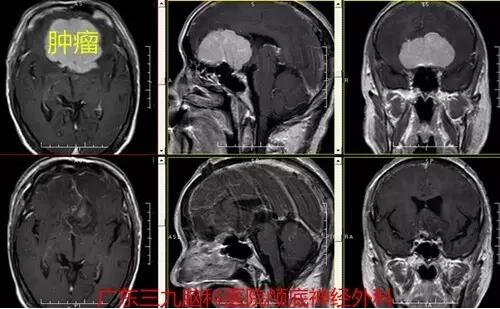

图2:术前磁共振显示肿瘤大小约6.36cm×6.55cm×3.56cm,强化明显

图4.:术前术后磁共振对比肿瘤全切